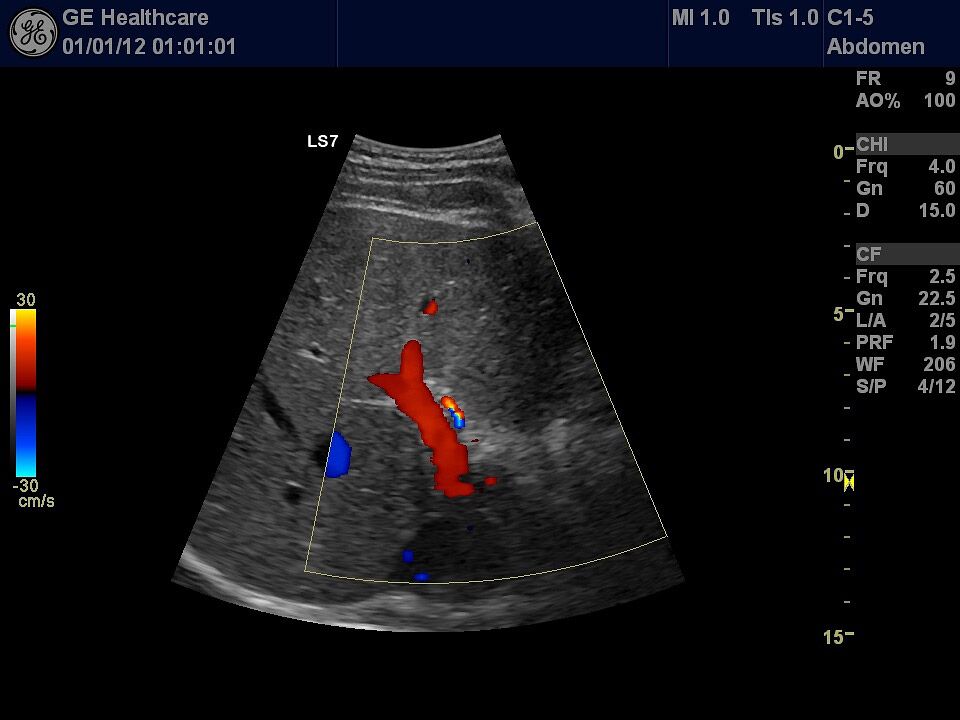

Die Ultraschall-Untersuchung ist mit Recht eine der wichtigsten und häufigsten Untersuchungsmethoden. Der Ultraschall ist ein bildgebendes Verfahren. Er erlaubt, von außen in den menschlichen Körper hinein zu sehen. So können die inneren Organe enorm detailreich und aussagekräftig untersucht werden. Vor allem die Weichteile wie Leber, Bauchspeicheldrüse, Galle, Niere oder Milz, die beim Röntgen nur schlecht zu sehen sind, können ausgezeichnet dargestellt werden.

Die Ultraschalluntersuchung ist ein sehr schnelles und leistungsstarkes Diagnoseverfahren. Dabei kann der Arzt Abläufe im Körper in Echtzeit sehen! Er hat keine Momentaufnahme vor sich, wie auf den Bildern des Röntgens oder der Computertomographie, sondern ein bewegtes Bild. Um zum Beispiel die Darmbeweglichkeit oder Organdurchblutung darzustellen, ein großer Vorteil. Da Sie als Patient dabei nicht in einer Röhre liegen, sondern ihr behandelnder Arzt neben Ihnen ist, kann ganz gezielt untersucht werden; dabei Beschwerdepunkte gezeigt, Befunde direkt erläutert und das weitere Vorgehen abgesprochen werden.